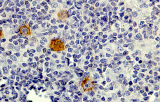

- LLC/LLS: co-espressione caratteristica di CD5 e CD23 nelle cellule B CD20+ (l'interpretazione richiede consapevolezza del pattern perché sono presenti cellule T reattive).